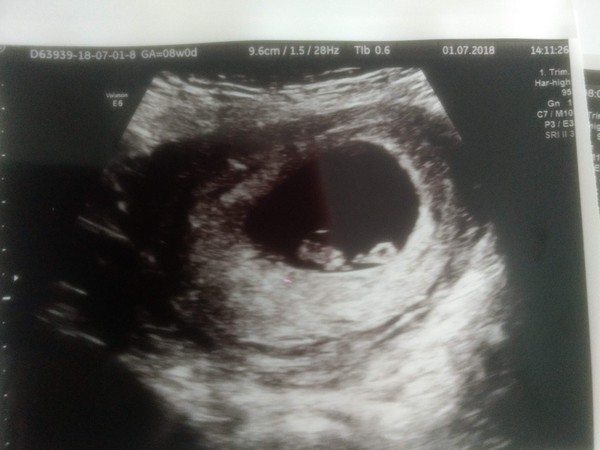

After saying I wasn't going to have a scan I booked and had one today, the panic over spotting was really upsetting me, you can't see a lot but she said you could see where the bleeding was coming from - 'a heterogeneous area' it says on my report, she said it looked small and should resolve but now I'm paranoid over that!

You can see the baby and the yolk sac in the photo, she said baby measured at 7 + 3 which is 3 days less than I thought so not far off.

@seafoodeatit you must feel so much better! Lovely scan photo 👌